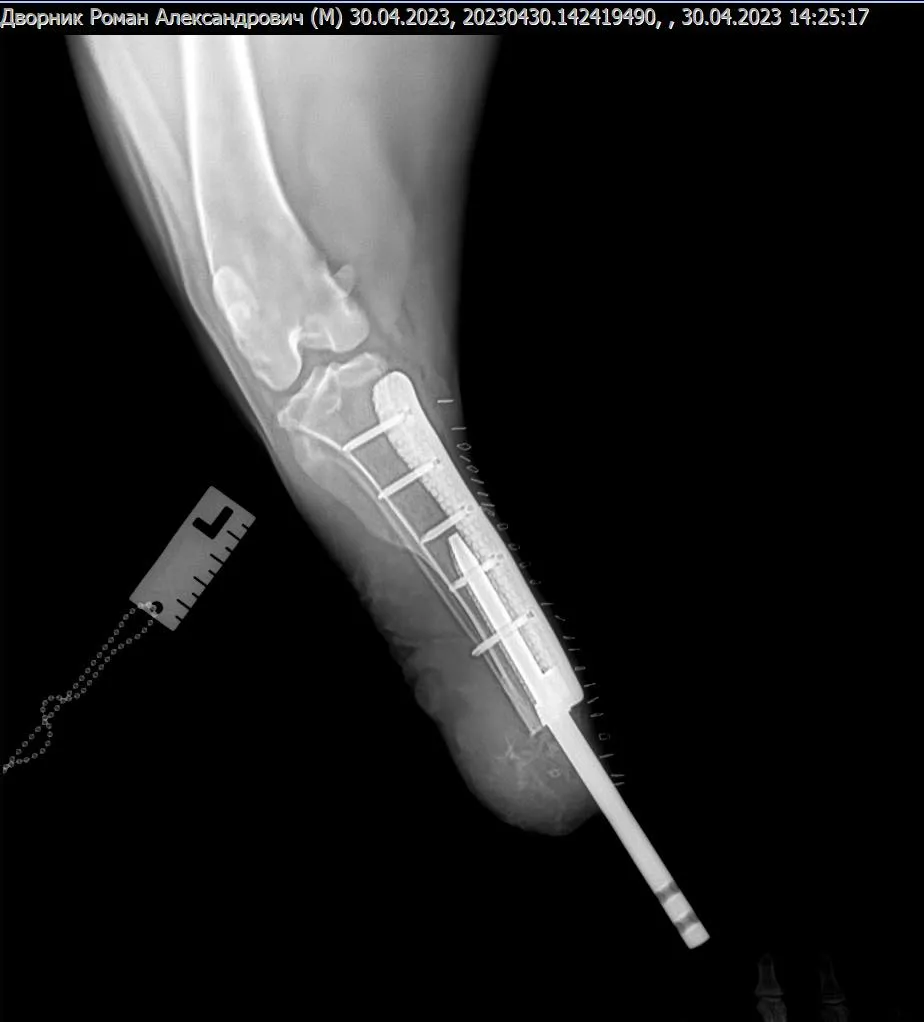

Лікарі Харківського ветеринарного шпиталю вперше провели операцію з біоінтегрованого протезування кінцівки у собаки. За словами головного лікаря шпиталю Віталія Клубаня, це пес породи російський чорний тер’єр, вагою 56 кг, який втратив лапу через російське бомбардування касетними снарядами під час прогулянки.

Спочатку собаку лікували в Києві, тому до харківських ветеринарів він потрапив уже із зашитими ранами. Сам імплант встановили на базі Салтівської ветеринарної клініки. Протез розробила українська компанія 3D Metal Tech, що виготовляє хірургічні імпланти із титанового сплаву методом 3D-друку.